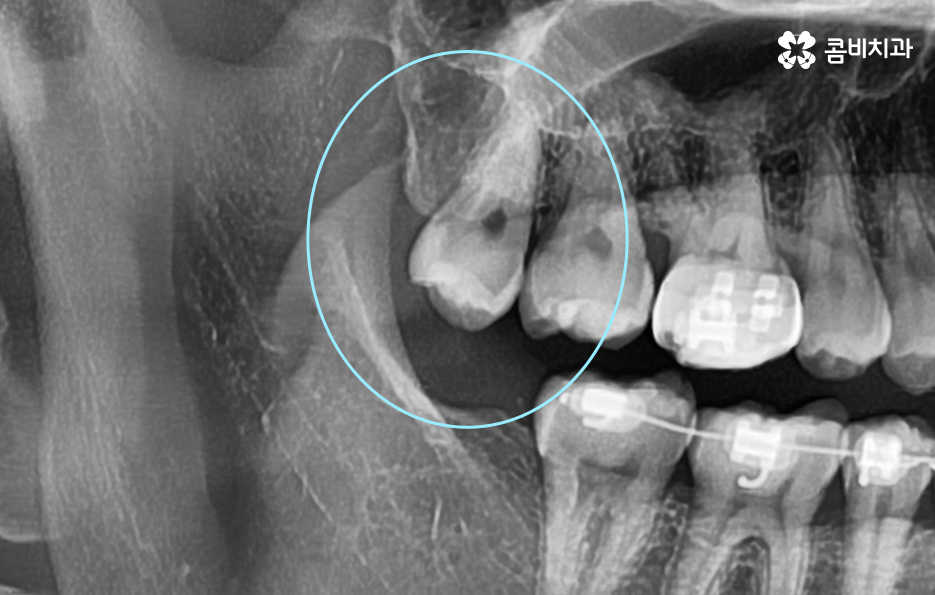

그럼에도 다들 사랑니는 일찍 뽑는게 낫다고 하던데 꼭 발치해야 하는 사례는 언제일지 살펴보면 이미 사랑니가 충치로 인해 많이 썩은 상태이거나 사랑니로 인해 주변 잇몸이 자꾸 붓고 염증이 발생하는 경우, 사랑니의 위치가 좋지 않아서 어금니의 뿌리 염증을 일으키거나 턱뼈 등의 손상이 예상되는 경우 등에는 꼭 발치를 해야하는 시점으로 볼 수 있어요

꼭 청결 관리의 이슈가 아니더라도 사랑니가 자라는 위치나 방향 자체가 좋지 않은 경우에는 문제가 예상되기 때문에 미리 발치하거나 이미 문제가 진행되고 있는 경우에는 사랑니 발치 시기 놓치지 말아야 더 큰 문제로 이어지는 일을 막을 수 있는데요.

현대인들은 사랑니의 위치가 좋지 않아서 주변 치아와 잇몸에 염증이 발생되는 사례가 많고 특히 하악에 매복 사랑니가 있는 경우가 많은데 완전히 누워서 자라는 사랑니는 발치 자체도 어렵지만 뿌리가 깊어지기 전에 발치하는 것이 발치나 회복에도 수월하기 때문에 정확한 사랑니 발치 시기의 골든타임을 놓치지 않기 위해서도 사랑니가 나올 무렵에 자신의 사랑니가 어떻게 자라고 있는지 확인하실 필요가 있어요